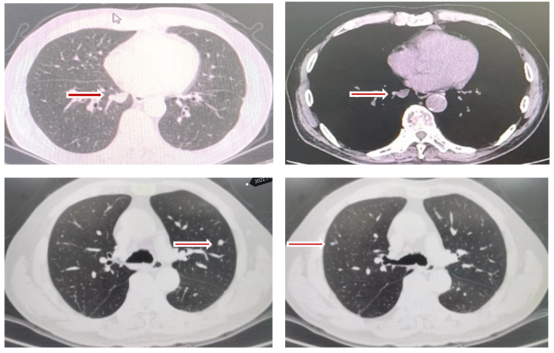

第一阶段治疗:2021年5月至2021年7月

胃肠肿瘤MDT讨论认为患者的原发病灶及转移灶是可切除状态,但生物学行为较差,经医患沟通后,决定先行西妥昔单抗+mFOLFOX6方案转化治疗再复查评估,外科手术治疗后再继续围手术期治疗。患者于2021年5月6日至2021年7月2日接受西妥昔单抗+mFOLFOX6治疗5周期;期间复查腹部及盆腔MRI,提示肝右后叶占位较前缩小(图3上),直肠管壁及周围改变较前缩小(图3下)。疗效评价:部分缓解(PR)。

图3 腹部MRI(上)、盆腔MRI(下)